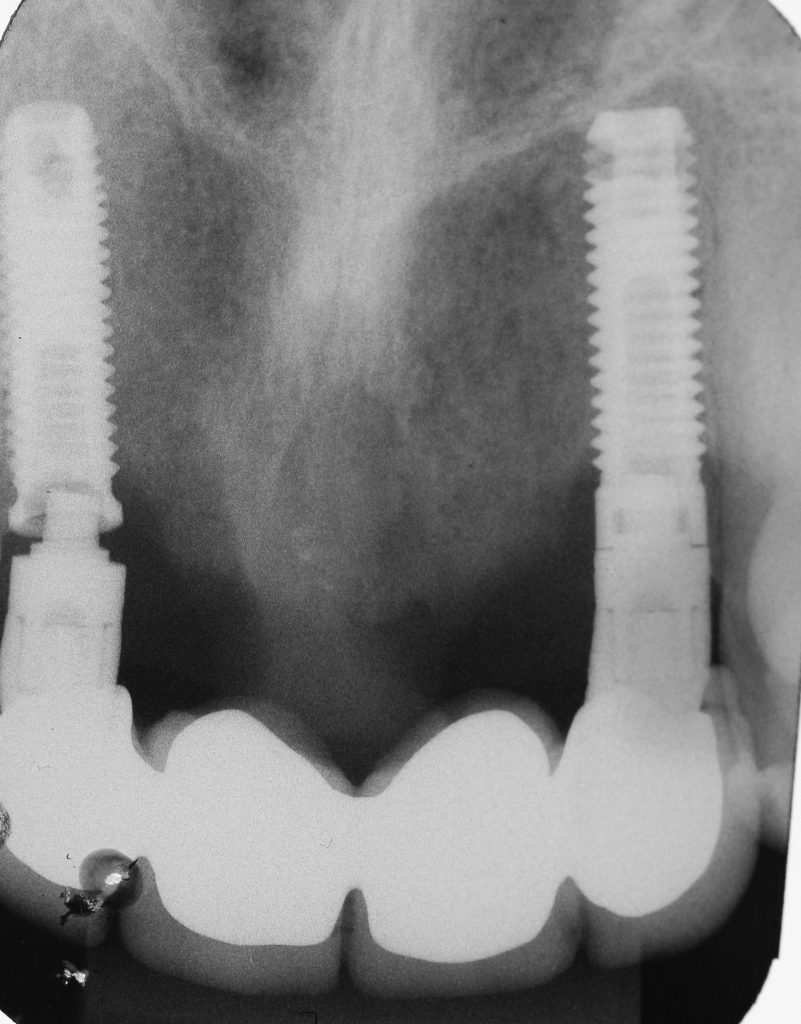

Explantation of an Anterior Implant with Excessive Buccal Inclination and Loss of Tissue Dental Implant Explantation Implantation in previously failed sites irrespective of an early or late failure results in 71% to 100% survival over 5 years. Dental implants, which are mobile or show only little residual bone‐to‐implant contacts, can usually be removed with instruments, which. It is valid for the whole straumann® dental implant. A systematic review of explantation techniques for osseointegrated dental implants revealed. Dental Implant Explantation.